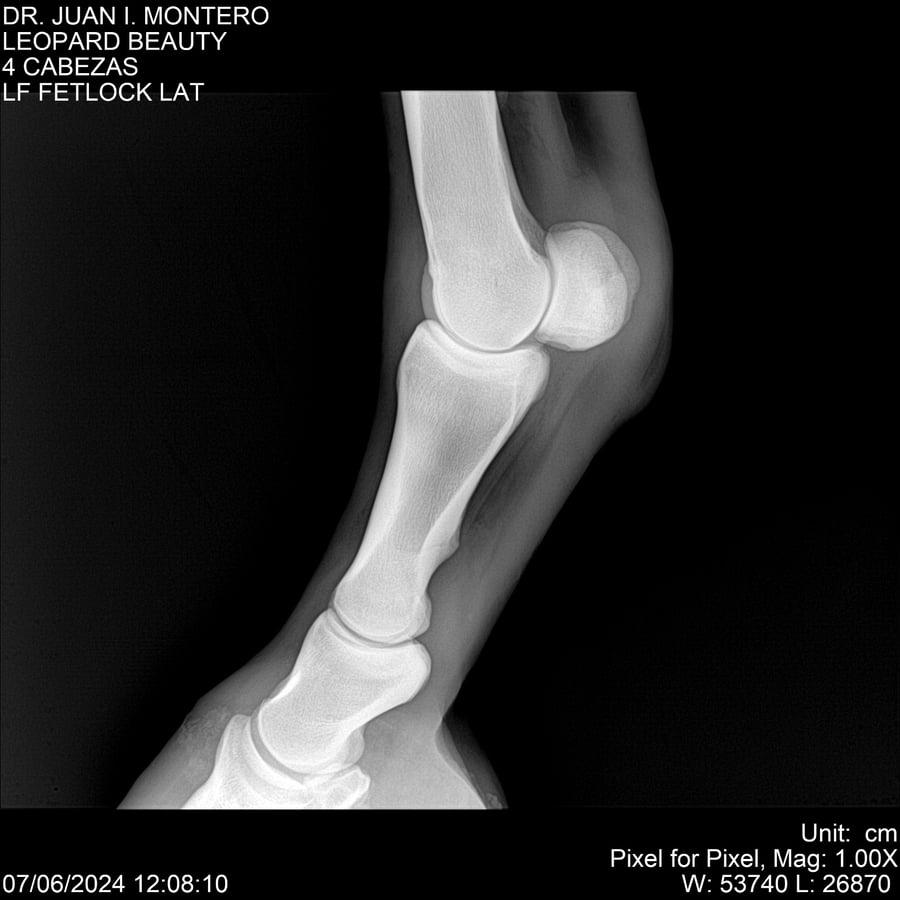

LOTE 16, LEOPARD BEAUTY Lote Anterior Volver al remate Lote Siguiente Ficha Contacto Montevideo - Ficha del Lote Identificador: #281095 Categoría: Yeguarizos Montevideo - 50 Visualizaciones ClicData Contacto Empresa: Abelenda N. R., Walter Hugo Nombre*: Teléfono* : E-mail* : Mensaje Enviar Registrese gratis Este contenido Exclusivo está disponible sólo para usuarios registrados Ingresar